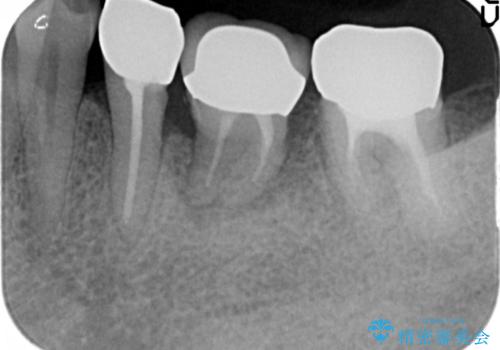

移植後、生着を待って根管治療及び補綴修復を行いました。

機能していない親知らずを用いて咬合を回復することができ、喜んで頂けました。

被せ物の種類:メタルボンドクラウン エコノミー